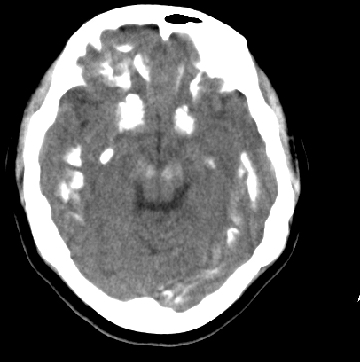

女性 38岁 病人脚弓反张 8岁以后不能行走 今年查pth11.9ng/ml(正常28ng/ml)

这么弥漫的钙化还第一次见。

考虑甲状旁腺功能减退症,该病是因甲状旁腺激素分泌减少或功能障碍所引起的少见病。其特点是低血钙,高血磷,且血pth极低。因低钙常可引起神经精神激惹症状,包括手指,趾,口角麻木,严重时可出现肌肉痉挛,喉哮鸣和惊厥,甚至癫痫样发作,有的可出现抑郁症及精神失常。长期的高磷血症可引起脑内结构对称性多发性钙化,特别是小脑和基底节的钙化可致锥体外系症状,而钙化的ct表现为类似于脑出血的密度增高影。

鉴别诊断:fahr 病,又称特发性家族性脑血管亚铁钙沉着症,是一种少见病,男女发病无显著差异,多为散发。临床表现为阵发性意识不清,首发症状开始于14~51 岁不等,以后呈阵发性发作,表现为突然神志丧失、跌倒、四肢抽搐约,发作后常表现为意识淡漠,性格改变,血清钙在正常范围。ct表现尾状核头呈倒“八”字形或片状钙化,在大脑半卵圆中心皮、髓质交界处多为点、小片状钙化,丘脑多呈对称小点、小条状钙化,小脑齿状核呈括弧形或不对称性小片状钙化。

原发性甲状旁腺功能减退症和fahr病都有神志上的改变等症状,且头颅ct检查均可见颅内出现钙化。但fahr病无pth低下,ct表现钙化影在大脑半卵圆中心皮髓质交界处、丘脑、小脑齿状核等处。 而甲状旁腺功能减退症pth极低,ct虽可见钙化影,但部位在小脑和基底节等处。